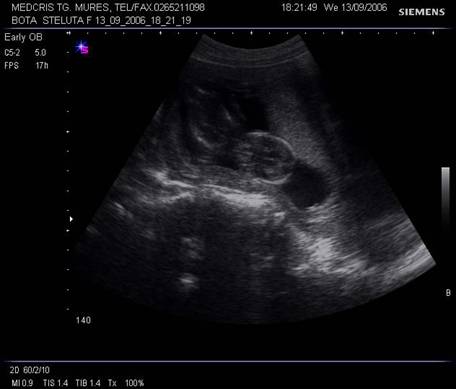

Fig. nr. 21. Aceeasi sarcina de 10 sapt., la ecografia abdominala